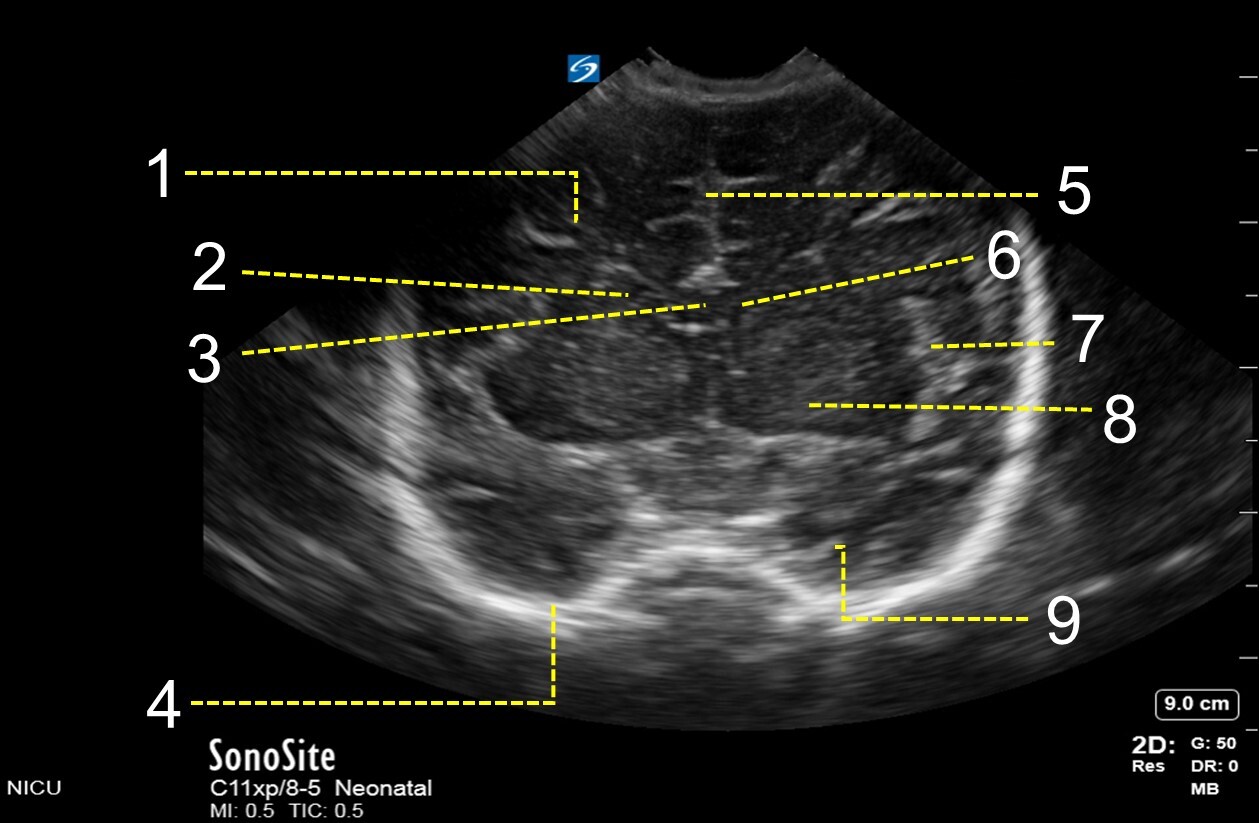

1. Frontal Lobe

2. Caudate Nucleus

3. Corpus Callosum

4. Skull

5. Interhemispheric Fissure

6. Frontal Horn of Lateral Ventricle

7. Sylvian Fissure

8. Basal Ganglia

9. Temporal Lobe